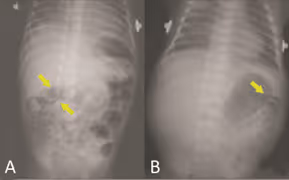

O diagnóstico é feito através da radiografia no abdômen do paciente e exame de sangue. A primeira pode demonstrar sinais de distensão, edema das alças intestinais e também a existência de gases na parede intestinal, condição conhecida como pneumatose intestinal.

A ocorrência da pneumatose sugere que existe perfuração da parede intestinal do RN, condição bastante grave que necessita de cirurgia e que pode até mesmo levar o bebê à óbito. O exame de sangue pode determinar a presença de bactérias ou demais anomalias na corrente sanguínea.

Radiografias mostram dilatação de alças e pneumatose intestinal na radiografia A. Na radiografia B ocorre a pneumatose intestina. Outro importante exame diagnóstico é o Teste de Apt, utilizado para identificar se o sangramento do trato intestinal do recém-nascido ocorre no órgão ou por causa da deglutição do sangue materno no momento da amamentação, o que ocorre com frequência quando há uma fissura na mama da lactante.